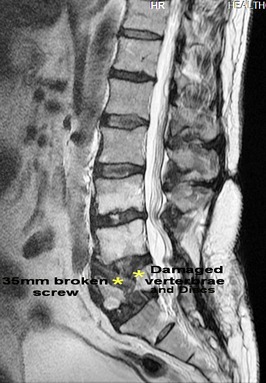

Yes Juergen I do. I had burns to 55% of mainly the top half my body and they scrapped skin for grafting from my legs. I do not have that many working sweat glands so aircon is a real necessity. My L4 & L5 were crushed and put back together with metal screws and rods. Unfortunately one of the 6 titanium screws broke and let the "Super Bugs" back in so they opened my back and took the metal out leaving the last 35mm of the broken screw. They did not want to gouge that bit our for fear of forcing super bugs into spinal column. I cannot walk any further than 100 meters, or stand for more than several minutes, and spend 80% of my waking hours in a comfortable lounge chair. Next job for van is to have club lounge taken out and 2 very comfortable lounge chairs fitted to suit my needs. Need to be comfortable OR I might crack the s***s and not go and THAT would be a shame for both of us!!